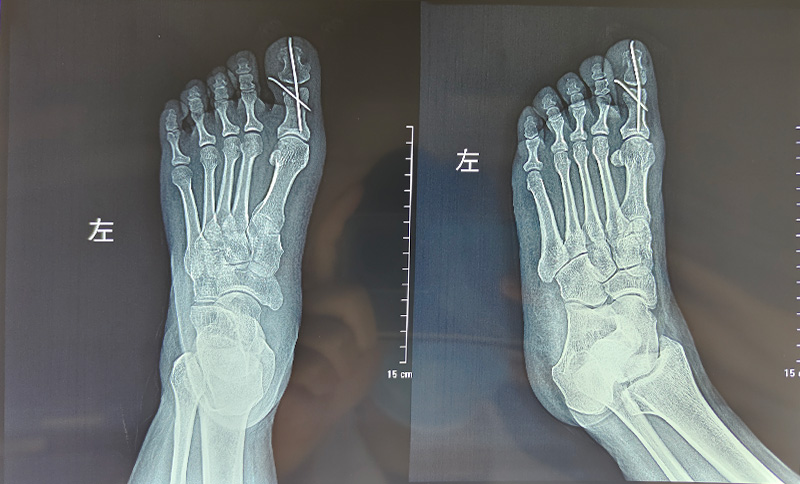

另一个病例是一位43岁的女性患者。因意外砸伤,导致左侧拇趾疼痛肿胀30分钟来院就诊。经详细检查,诊断为“左侧拇趾趾骨骨折”。骨三科医护团队在局部麻醉下,为其顺利开展了“左侧拇趾趾骨骨折闭合复位内固定术”。手术创伤小、用时短,术后患者疼痛明显缓解,对治疗效果给予了高度认可。

术后